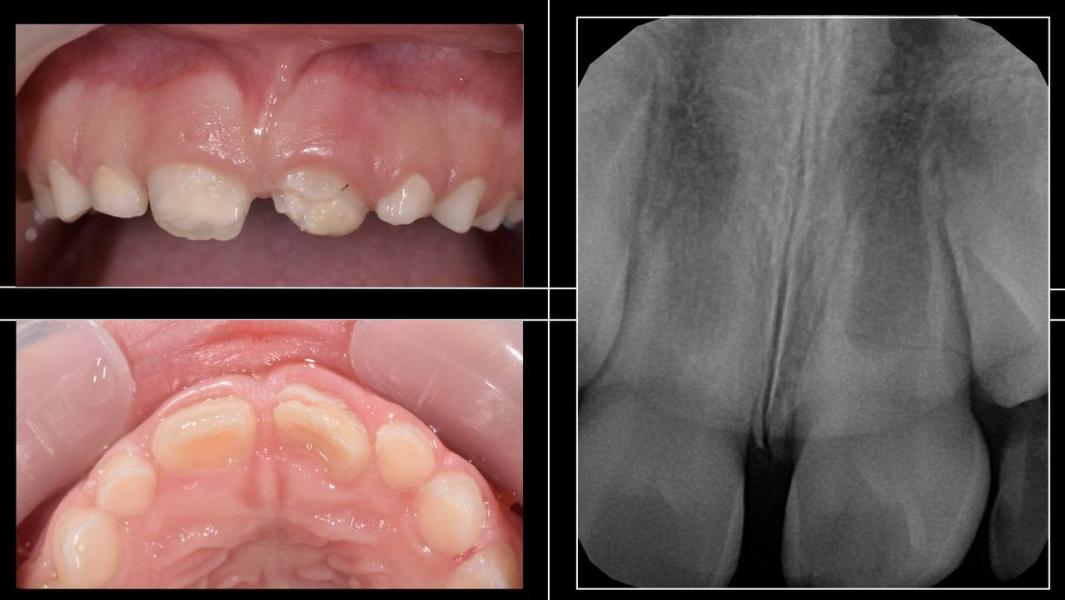

Девочке 7 лет.

Около 6 дней до обращения к нам, упала в бассейне и получила травму, ударившись зубами о кафель.

Диагноз: коронково- корневой перелом 21.

Было принято решение об аутотрансплантации

63➡21

Т.к. зуб к сожалению, уже нельзя было спасти (зуб сломался ниже уровня кости, а аутотрансплантация позволяет сохранить кость и восстановить эстетику).